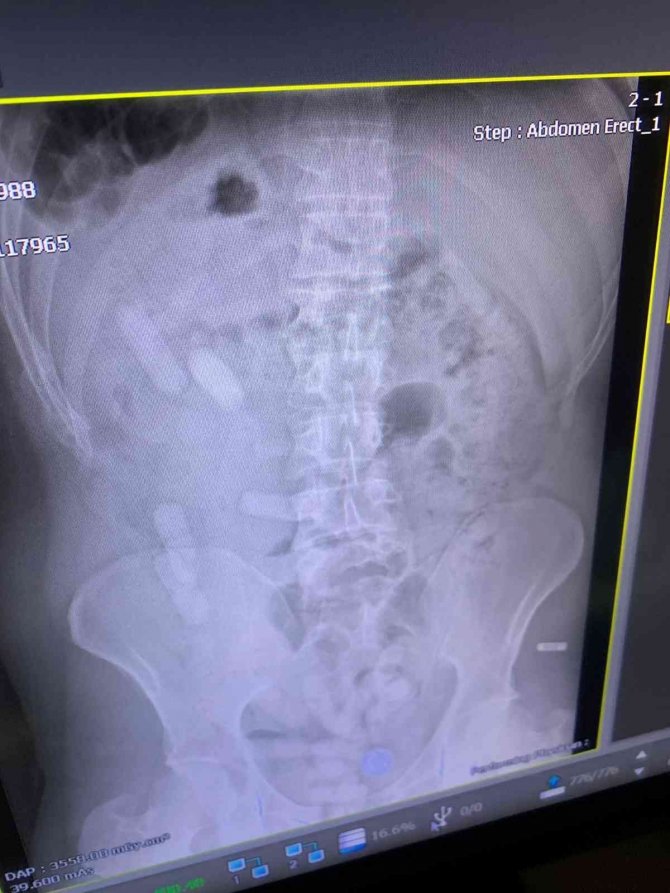

Edinilen bilgiye göre Sivas İl Jandarma Komutanlığı ekipleri, D-100 karayolu Yıldızeli ilçesi geçişinde Lasy isimli narkotik köpeği ile yol denetimi gerçekleştirdi. İranlı yolcuları taşıyan 84 AA 845 plakalı otobüste yapılan aramada A.E. (34) isimli şahsın üzerinde, içerisinde reçine esrar bulunan 140 kapsül ele geçirildi. Şüphe üzerine A.E. isimli İranlı şahsa çekilen röntgen filminde midesinde de 15 kapsül olduğu anlaşıldı. Kapsüller doğal yollarda çıkartıldı. A.E. jandarma ifadesinin ardından çıkartıldığı adli makamlarca tutuklanarak cezaevine konuldu.